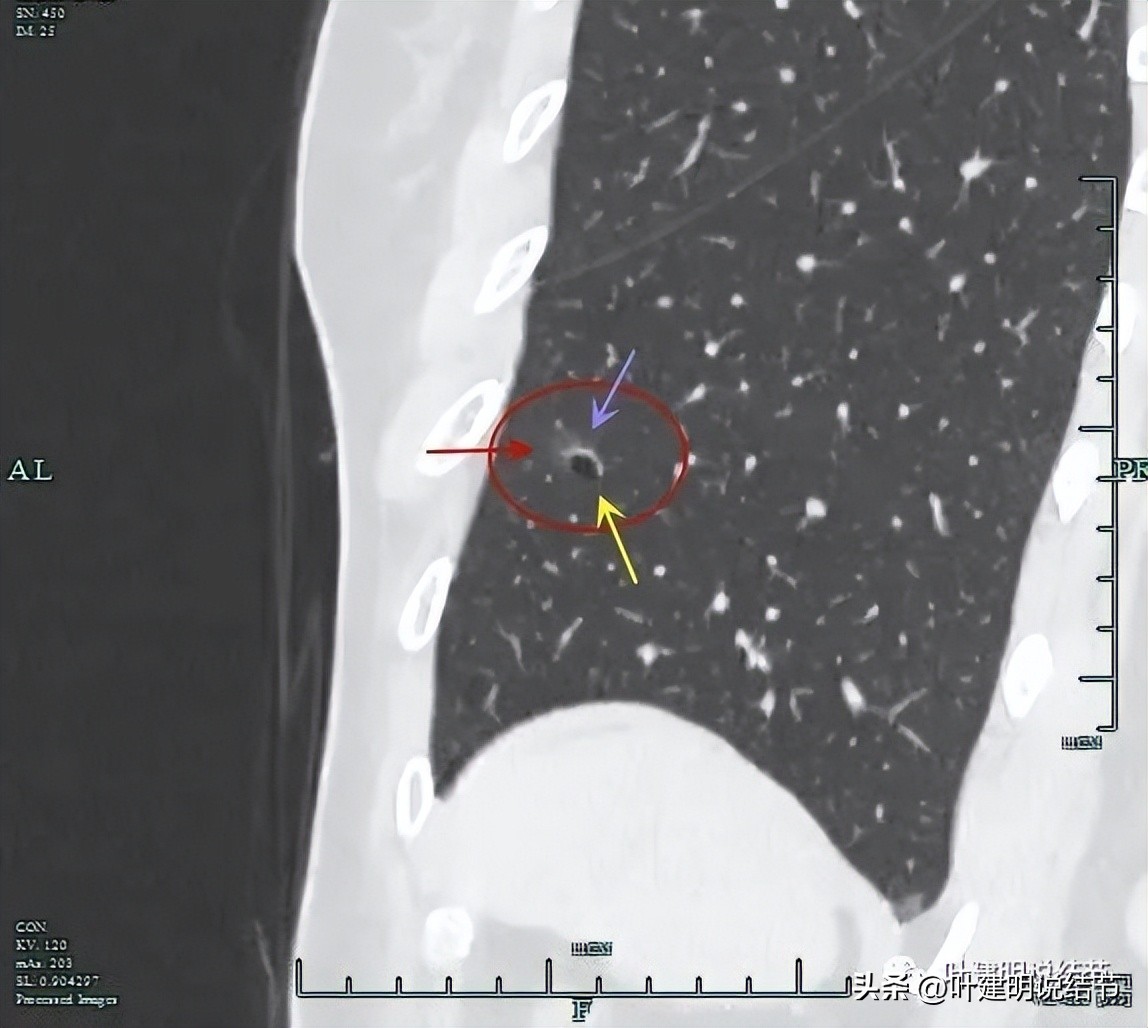

再看左下叶的主病灶,此层见其是磨玻璃密度,轮廓较清,内部密度欠均匀。

有明显血管征,血管进入后有分支发出,病灶表面显得有毛刺样。

病灶中间有空腔。

囊壁较薄,但不均匀,有的地方还是显略厚了点的。

似乎见微小血管走向病灶。

微小血管征确实有。

靶重建后发现病灶囊腔型,桔色箭头示进入的血管有异常增粗,而且壁显得毛糙;黄色箭头示空腔;红色箭头示整体轮廓较清;绿色箭头示有磨玻璃成分,虽然密度较低;蓝色箭头示病灶略有胸膜牵拉影响,只是力较弱而已。